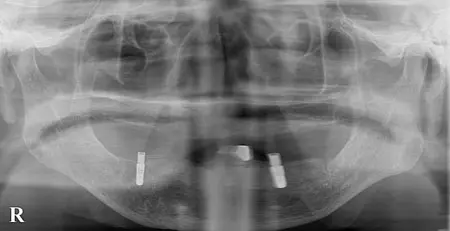

2025.10.0290代男性「他院にて下顎作製したが合わず痛い。食事がとれない。」下顎の前歯部にインプラントを2本埋入し、しっかりと噛めるようになった症例